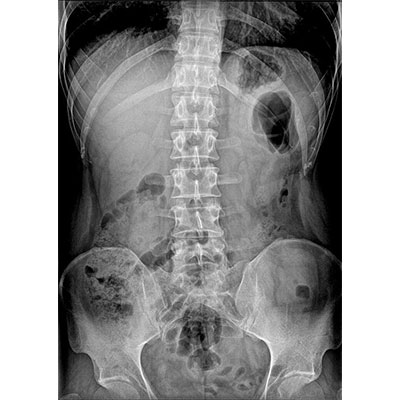

● 采用自主研發的技術,在保證優質圖像的前提下,大大降低X射線劑量,用心呵護醫護工作者及患者的健康。

● 短曝光時間,便于老年人、兒童、殘疾人進行臨床拍攝。避免這類群體因不能有效控制身體運動等因素造成的運動偽影,提高攝片質量及效率。

智能化運動系統支持一鍵到位,一鍵完成臥位到站立位的智能切換,并自動調整適合的SID,平板自主對中校準,準確到達預投照體位。